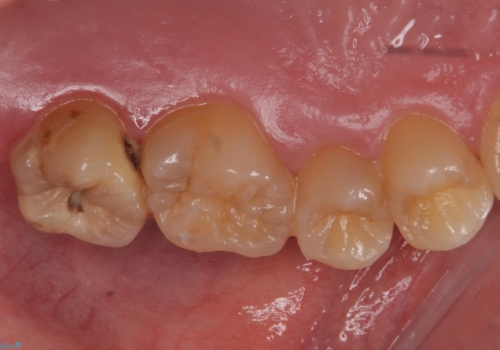

- 奥歯に穴が開いた気がするとのことで来院。

検査の結果、左上の奥歯に大きな虫歯があることが確認できました。

患者様のご希望もあり、今回はセラミックでの治療となりました。